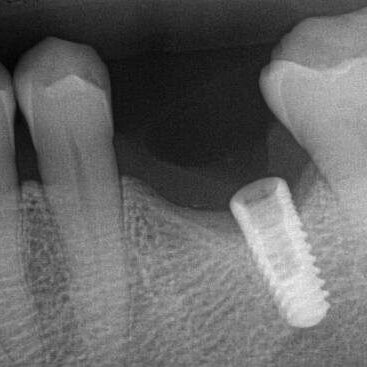

ULTRASONICS: Complications of Abutment Screw Retrieval Secondary to Prior Ultrasonic Attempts

There has been much written on the use of ultrasonics in retrieving fractured screw fragments, which I didn’t think a lot about until May of 2023, as it has not been a part of my fractured screw retrieval algorithm.